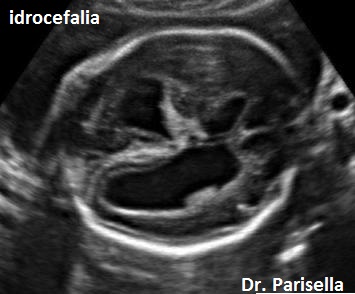

Possono essere presenti: 6) piede torto; 7) idrocefalia.